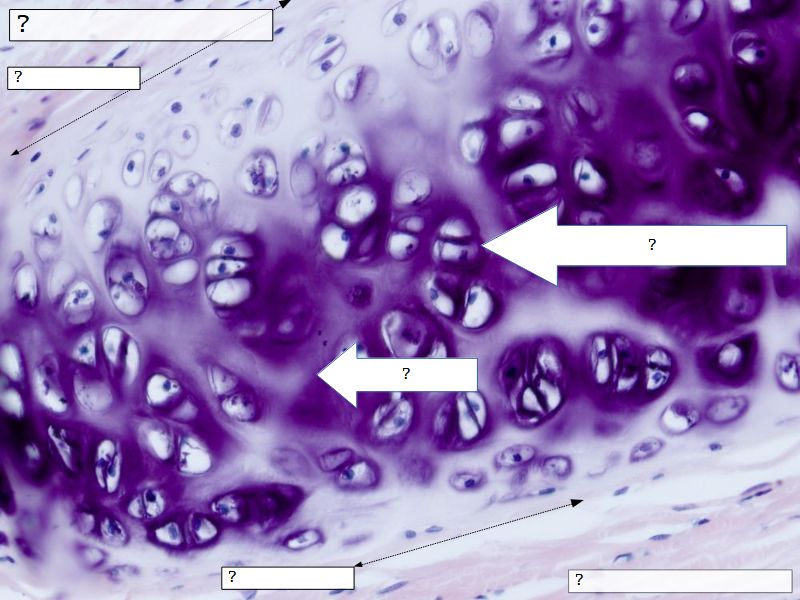

Fill in all the missing labels, and assess as you move through the slides. Answers on the down slide. It is important to do this using pen and paper, and not just glance through the images.